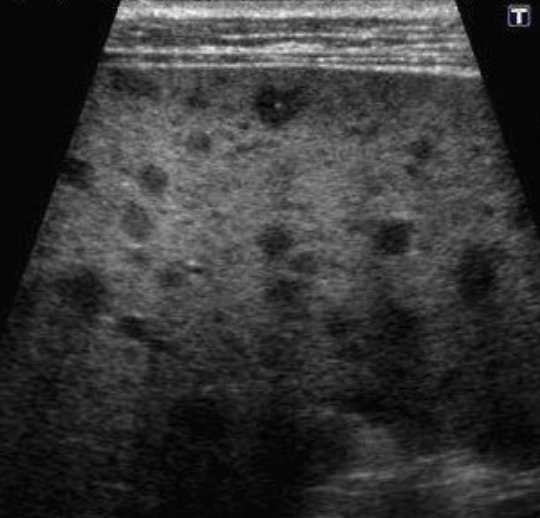

Metastatic Disease (METS) → most common form of neoplastic involvement of the liver

2D US: single or multiple solid lesions, varying sizes, can have bullseye appearance, echogenic, or hypoechoic, enlarged liver, can cause pseudo nodularity

color doppler: hypo to hypervascular

DDX: HCC, hemangioma, lymphoma